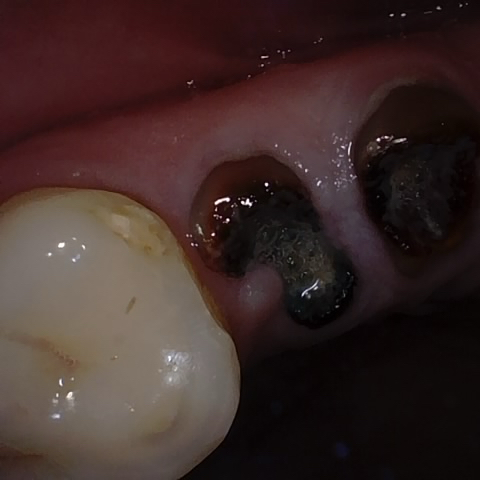

Annotated as "Good"